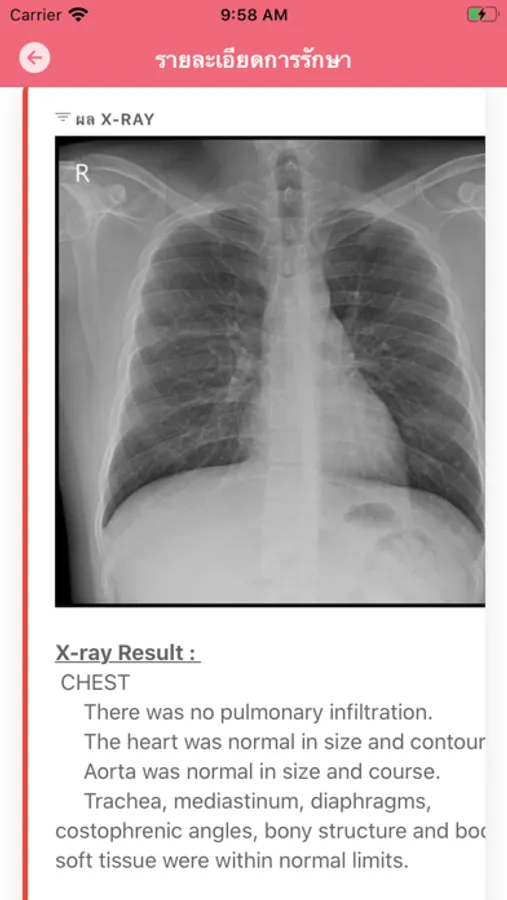

ระบบข้อมูลสุขภาพส่วนบุคคล (Personal Health Record : PHR) สำหรับโรงพยาบาลในเครือ เพื่อให้ผู้ป่วยสามารถติดตามประวัติการรักษา, ข้อมูลอาการป่วย, การใช้ยา, การใช้สิทธิ์เบิกค่ารักษาต่างๆ และแนวโน้มสุขภาพ เพื่อให้ผู้ป่วยสามารถติดตามและดูแลสุขภาพได้ด้วยตนเองอย่างต่อเนื่อง